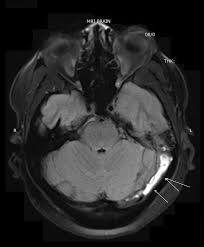

Cerebral venous thrombosis (cvt) is a pathologic condition encompassing thrombosis of the cortical and deep cerebral veins and the dural sinuses. Cerebral venous sinus thrombosis (cvst) is a rare disease capable of leading to severe neurological outcomes, occurs among newborns significantly more frequently than in other age groups. Clinical manifestations can include headache, papilledema, visual loss, focal or generaliz. Recommendations on the evaluation and management of cerebral venous thrombosis during pregnancy and in the pediatric population are provided. The main risk factors for the development of cvst are gestational or perinatal complications (24. Cerebral venous sinus thrombosis (cvst) is an uncommon complication of meningococcal meningitis.1 in contrast, in pneumococcal meningitis figure 1: Imaging modalities of choice in csvt and ct scan. What causes cerebral venous sinus thrombosis? Cerebral venous thrombosis (cvt) is an uncommon disorder in the general population. Cvst is an uncommon type of stroke. Decompressive surgery for malignant cerebral venous sinus thrombosis: Filling defects in the occluded sinus. Ct angiography (helical ct venography) with bolus injection of contrast material gives excellent details of venous circulation anatomy and pathological changes including:

Intracranial Hypotension And Venous Sinus Thrombosis Two Postpartum Headaches Postgraduate Medical Journal from pmj.bmj.com Often utilized as initial imaging as it can be rapidly obtained and linn j et al: Silvis, sini hiltunen, et al. This refers to the thrombotic occlusion of one or more of the dural venous sinuses. Cerebral venous sinus density on noncontrast ct correlates with hematocrit. Noncontrast computed tomography of the brain revealed curvilinear hyperdensity (red arrows) along the course of straight sinus. For the cerebral venous sinus thrombosis study group. Thrombosis of cerebral veins and venous sinuses is a rare disease, which accounts for less than 1% of all cases of stroke. This condition may also be called cerebral sinovenous thrombosis.

Cerebral venous sinus thrombosis occurs when a blood clot forms in the brain's venous sinuses. For the cerebral venous sinus thrombosis study group. Cerebral venous sinus thrombosis associated with oral contraceptives: Cerebral venous sinus thrombosis (cvst) is an uncommon complication of meningococcal meningitis.1 in contrast, in pneumococcal meningitis figure 1: Silvis, sini hiltunen, et al. Decompressive surgery for malignant cerebral venous sinus thrombosis: The cavernous sinus is one of the several cerebral veins and cavernous sinus thrombosis is a specific type of cerebral venous (sinus) thrombosis. Hanprasertpong t., hanprasertpong j., riabroi k. Cvst is a rare form of stroke. Cerebral venous thrombosis in the absence of headache. The mainstay of management is. The most frequent and often early symptom of thrombosis of cerebral veins and sinuses is a headache. Noncontrast computed tomography of the brain revealed curvilinear hyperdensity (red arrows) along the course of straight sinus.

Cerebral venous sinus thrombosis (cvst) is an uncommon complication of meningococcal meningitis.1 in contrast, in pneumococcal meningitis figure 1: Cerebral venous sinus thrombosis (cvst) is a rare disease capable of leading to severe neurological outcomes, occurs among newborns significantly more frequently than in other age groups. Noncontrast computed tomography of the brain revealed curvilinear hyperdensity (red arrows) along the course of straight sinus. Filling defects in the occluded sinus. Cerebral venous thrombosis (cvt) is an uncommon disorder in the general population.

Imaging Of Cerebral Venous Thrombosis Clinical Radiology from els-jbs-prod-cdn.jbs.elsevierhealth.com An unusual diagnosis and management of cerebral venous thrombosis: Cerebral venous sinus thrombosis as presenting feature of ulcerative colitis. Efns guideline on the treatment of cerebral venous and sinus thrombosis. Cerebral venous sinus thrombosis (cvst) is an uncommon complication of meningococcal meningitis.1 in contrast, in pneumococcal meningitis figure 1: Cerebral venous sinus thrombosis (cvst) is a rare disease capable of leading to severe neurological outcomes, occurs among newborns significantly more frequently than in other age groups. Residents and fellows contest rules | international ophthalmologists contest rules. Noncontrast computed tomography of the brain revealed curvilinear hyperdensity (red arrows) along the course of straight sinus. Thrombosis of cerebral veins and venous sinuses is a rare disease, which accounts for less than 1% of all cases of stroke.

Cerebral venous sinus thrombosis as presenting feature of ulcerative colitis. Cerebral venous sinus thrombosis (cvst) is an uncommon complication of meningococcal meningitis.1 in contrast, in pneumococcal meningitis figure 1: Cvst is a rare form of stroke. Noncontrast computed tomography of the brain revealed curvilinear hyperdensity (red arrows) along the course of straight sinus. Cerebral venous sinus density on noncontrast ct correlates with hematocrit. Silvis, sini hiltunen, et al. Cerebral venous sinus thrombosis (cvst) is the presence of a blood clot in the dural venous sinuses, which drain blood from the brain. Filling defects in the occluded sinus. Cerebral venous thrombosis (cvt) is an uncommon but serious disorder. Cvst is an uncommon type of stroke. The cavernous sinus is one of the several cerebral veins and cavernous sinus thrombosis is a specific type of cerebral venous (sinus) thrombosis. The most frequent and often early symptom of thrombosis of cerebral veins and sinuses is a headache. Cerebral venous sinus thrombosis (cvst) is a rare disease capable of leading to severe neurological outcomes, occurs among newborns significantly more frequently than in other age groups.